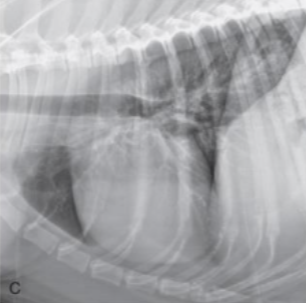

| Generalized cardiomegaly |

|---|

| RA, RV, LA, LV๊ฐ ๋ค ์ปค์ง โ Globoid heart |

| - Pericardial effusion - ์ฌํ ์์ชฝ ์ฌ์ฅ๋ณ (MVI + TVI) - PPDH (Peritoneopericardial diaphragmatic hernia) - Cardiomyopathy (DCM) - Anesthesia, bradycardia |

![]() |